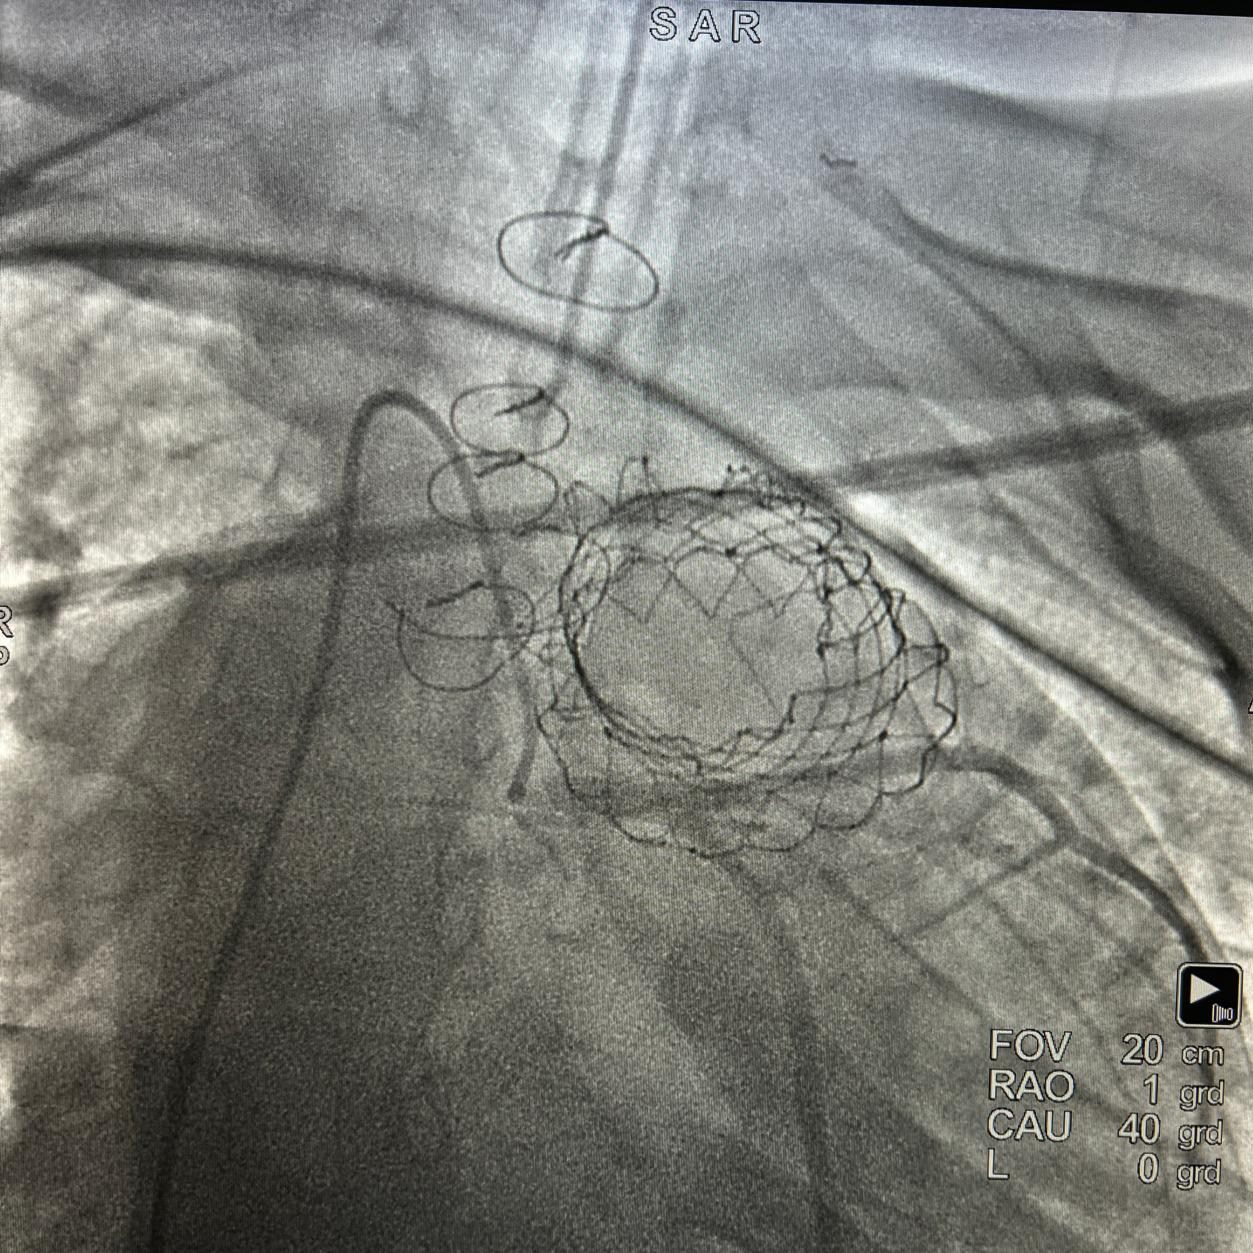

FVL instaló con éxito, por primera vez en Colombia, la válvula pulmonar Venus P

El objetivo principal del procedimiento es restituir la función de la válvula pulmonar, pues su insuficiencia genera disfunción y dilatación del ventrículo derecho, llevando a la incapacidad funcional total del paciente.

Es primera vez que esta válvula es puesta en una institución de salud de Colombia y entre sus principales beneficios se destaca la recuperación más rápida del paciente, quien al día siguiente puede ser dado de alta debido a la no intervención quirúrgica. El procedimiento fue realizado por nuestros especialistas en cardiología pediátrica el Dr. Walter Mosquera y el Dr. Jaiber Gutiérrez, junto a un grupo multidisciplinario del área.